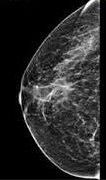

Mammograms are pivotal tools in the realm of breast health. As a cornerstone of breast cancer screening, understanding their significance and debunking associated myths is crucial for every woman’s well-being.

Mammograms are essential tools in the early detection of breast cancer, and yet, many myths and misconceptions surround them. These myths can lead to anxiety and reluctance among women when it comes to scheduling these potentially life-saving screenings. In this blog post, we’ll demystify mammograms by providing you with the facts you should know and debunking some common myths.

6. Image Capture: The technologist will step behind a protective barrier and activate the X-ray machine. The X-ray beam will pass through your breast tissue and onto the detector, creating an image of the breast. At least two images are typically taken for each breast, from different angles (usually top-down and side views). Additional images may be taken if the radiologist requires more detail.

Myth #3: Mammograms Always Detect Cancer

While mammograms are a valuable screening tool, they are not infallible. They may miss some cancers, particularly in women with dense breast tissue. However, this is why regular screenings are essential. Mammograms can detect many breast cancers at an early, highly treatable stage, which can be a life-saver. False positives, where the test suggests cancer when none is present, can also occur, leading to unnecessary anxiety and follow-up tests. However, the benefits of early detection far outweigh these limitations, as catching cancer in its early stages dramatically improves survival rates.